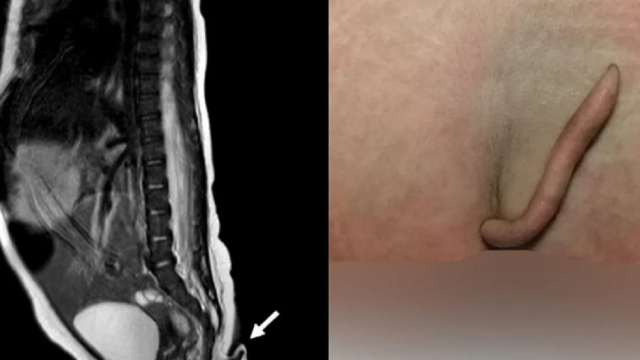

De acordo com informações divulgadas pelo Journal Of Pediatric Surgery Case Reports, uma menina nasceu com uma cauda de quase 6 cm de comprimento e coberta de pele e pelos finos. O caso aconteceu no México e se tornou um objeto de estudo, além de desafiar os limites da literatura médica nos dias atuais.

Segundo as observações relatadas no caso, a cauda não apresentava tecido ósseo dentro, apenas pele, músculos, nervos, tecido conjuntivo, vasos sanguíneos e gordura. A estrutura saía do final do cóccix com a base ligeiramente para a esquerda. Variava entre 3mm e 5mm de diâmetro, estreitando-se em direção à ponta. A menina foi submetida a uma ressecção cirúrgica para a retirada da cauda.

No caso da menina, tratava-se de uma cauda verdadeira. Acredita-se que essa estrutura emerja da cauda embrionária que todos os bebês desenvolvem no útero, mas geralmente é reabsorvida de volta ao corpo para formar o cóccix. As caudas geralmente não são detectadas até que o bebê nasça e os médicos não sabem exatamente o que o que causa o fenômeno.